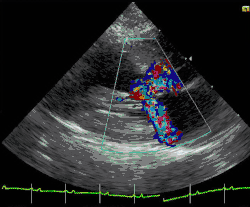

A diagnosis of hypertrophic cardiomyopathy is based upon several features of the disease process. While there is use of echocardiography, cardiac catheterization, or cardiac MRI in the diagnosis of the disease, other important considerations include ECG, genetic testing (although not primarily used for diagnosis),[33] and any family history of HCM or unexplained sudden death in otherwise healthy individuals. In about 60 to 70% of the cases, cardiac MRI shows thickening of more than 15 mm of the lower part of the ventricular septum. T1-weighted imaging may identify scarring of cardiac tissues while T2-weighted imaging may identify edema and inflammation of cardiac tissue which is associated with acute clinical signs of chest pain and fainting episodes.[34]

ECG is the most sensitive diagnostic test.[17] The combination of left ventricular hypertrophy, and right atrial enlargement on ECG strongly suggests HCM.[17]

Depending on whether the distortion of normal heart anatomy causes an obstruction of the outflow of blood from the left ventricle of the heart, HCM can be classified as obstructive or non-obstructive.[35] The obstructive variant of HCM is hypertrophic obstructive cardiomyopathy (HOCM), also historically known as idiopathic hypertrophic subaortic stenosis (IHSS) or asymmetric septal hypertrophy (ASH).[36] The diagnosis of left ventricular outflow tract obstruction is usually made by echocardiographic assessment and is defined as a peak left ventricular outflow tract gradient of ≥ 30 mmHg.[35]

HCM can be detected with an echocardiogram (ECHO) with 80%+ accuracy,[44] which can be preceded by screening with an electrocardiogram (ECG) to test for heart abnormalities. Cardiac magnetic resonance imaging (CMR), considered the gold standard for determining the physical properties of the left ventricular wall, can serve as an alternative screening tool when an echocardiogram provides inconclusive results.[45] For example, the identification of segmental lateral ventricular hypertrophy cannot be accomplished with echocardiography alone. Also, left ventricular hypertrophy may be absent in children under thirteen years of age. This undermines the results of pre-adolescents' echocardiograms.[15] Researchers, however, have studied asymptomatic carriers of an HCM-causing mutation through the use of CMR and have been able to identify crypts in the interventricular septal tissue in these people. It has been proposed that the formation of these crypts is an indication of myocyte disarray and altered vessel walls that may later result in the clinical expression of HCM.[45] A possible explanation for this is that the typical gathering of family history only focuses on whether sudden death occurred or not. It fails to acknowledge the age at which relatives had had sudden cardiac death, as well as the frequency of the cardiac events. Furthermore, given the several factors necessary to be considered at risk for sudden cardiac death, while most of the factors do not have strong predictive value individually, there exists ambiguity regarding when to implement special treatment.[46]